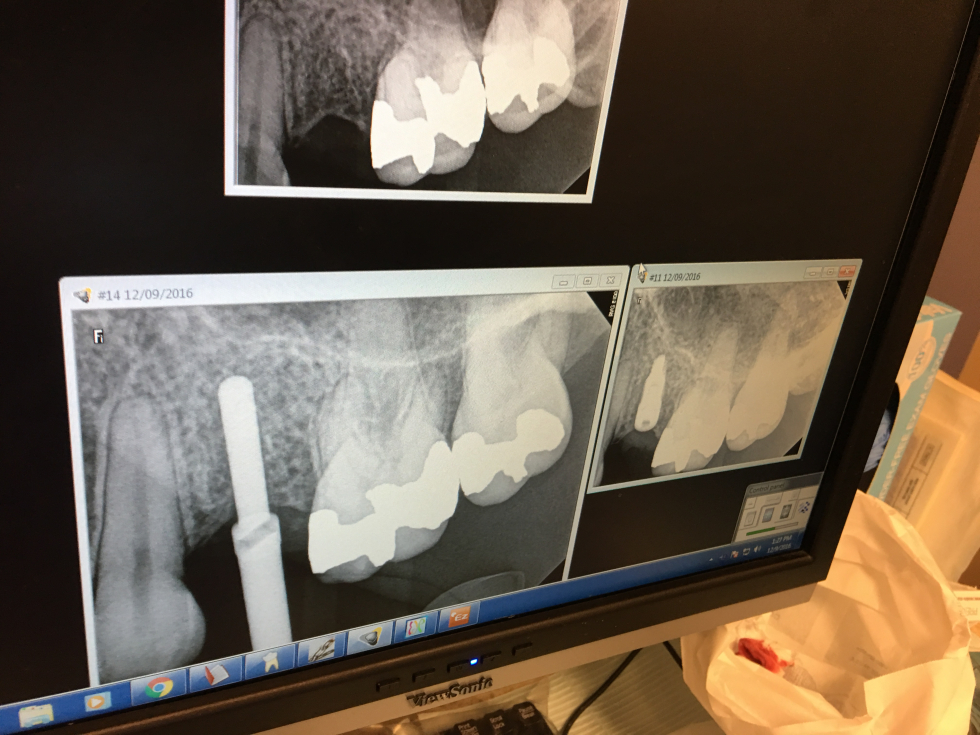

The North-East and Mid-Atlantic Regions hosted its first regional sales meeting on Dec 9 and 10.

The event included live surgery using Sweden & Martina Premium and Shelta implants, MISE sinus elevation kit, bone grafting, Ossix Plus membrane

and Sweden & Martina sutures.